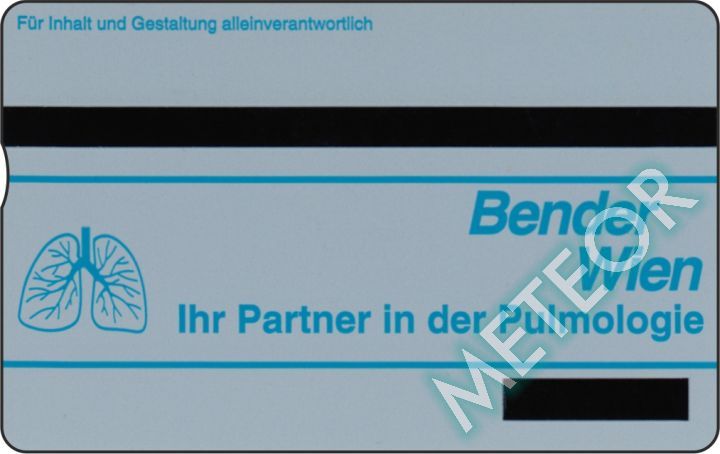

Meteor-Code: TKA P358

ANK-Nummer: P 358

Herausgeber: Telekom Austria

Auflage: 1.000

Seriennummer: 408L 02000 - 02999

Schlagworte: Pharmazie